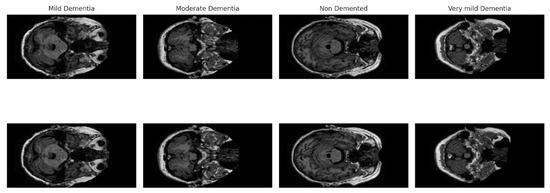

NeuroFusion-ViT: A Hybrid CNN–EVA Transformer Model with Cross-Attention Fusion for MRI-Based Alzheimer’s Stage Classification

by Derya Öztürk Söylemez and Sevinç Ay Doğru

Diagnostics 2026, 16(5), 754; https://doi.org/10.3390/diagnostics16050754 - 3 Mar 2026

Background: Alzheimer’s disease is the most common type of dementia and a progressive neurodegenerative disease that begins with neuronal damage and leads to a reduction in brain tissue. Currently, there is no cure for this disease, and existing approaches focus on alleviating symptoms. Methods: This study proposes NeuroFusion-ViT, a highly accurate and computationally efficient hybrid deep learning model for early-stage detection of Alzheimer’s disease. The model combines an EVA-02-based Vision Transformer (ViT) with the ConvNeXt-Small CNN architecture, providing powerful representation learning that can process both global context and local details. The proposed Gated Cross-Attention Fusion (G-CAF) mechanism dynamically combines two different features, offering high discriminative power and model stability. Results: In experiments conducted on the OASIS MRI dataset, the model achieved 99.86% accuracy, 0.9989 Macro F1, and 0.999 ROC-AUC values, demonstrating clear superiority over single-modal and hybrid models described in the literature. Furthermore, 5-fold cross-validation results also support the model’s high generalizability. Ablation studies showed that each of the components—cross-attention, gate mechanism, Dual LayerNorm, and FFN-Dropout—made a meaningful contribution to performance. Conclusions: The results demonstrate that the NeuroFusion-ViT architecture offers a reliable, stable, and clinically applicable solution for Alzheimer’s stage classification. Full article